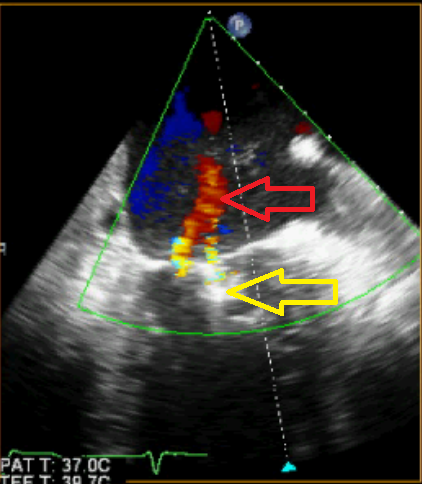

Video 2 – Slokdarmechocardiografie ná mitraclipbehandeling, 2-kamer opname linkerventrikel. Met color doppler is er nog een milde insufficiëntie zichtbaar.

Figuur D –  Slokdarmechocardiografie, 2-kamer opname linkerventrikel. De rode pijl geeft de milde mitralisklepinsufficiëntie aan. Vergeleken met figuur C is er een aanzienlijke reductie van de lekkage. De gele pijl geeft de lokalisatie aan van de MitraClip